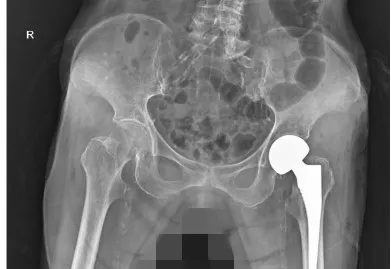

各项术前准备工作充分完成后,在麻醉科的密切配合下,外科手术团队为曾奶奶圆满完成了髋关节置换手术,术后在医护团队的精心照料与专业指导下,曾奶奶逐渐在助行器的帮助下重新迈出步伐,经过一周的治疗顺利康复出院。

▲术后DR显示:假体位置良好